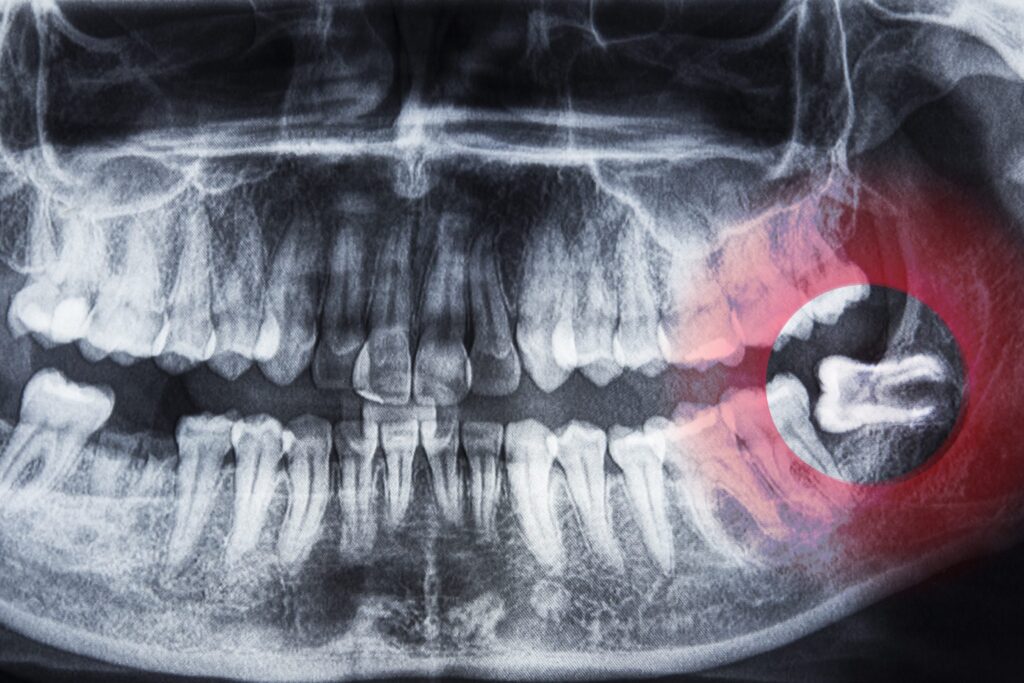

¿Cuándo hay que extraer las muelas del juicio?

La erupción de las muelas del juicio es un temor muy común entre las personas, pues muchas creen que va directamente relacionado con una extracción, pero lo cierto es que, en la mayoría de los casos estas erupcionan y se alinean perfectamente con el resto de los dientes. En este artículo te vamos a contar […]